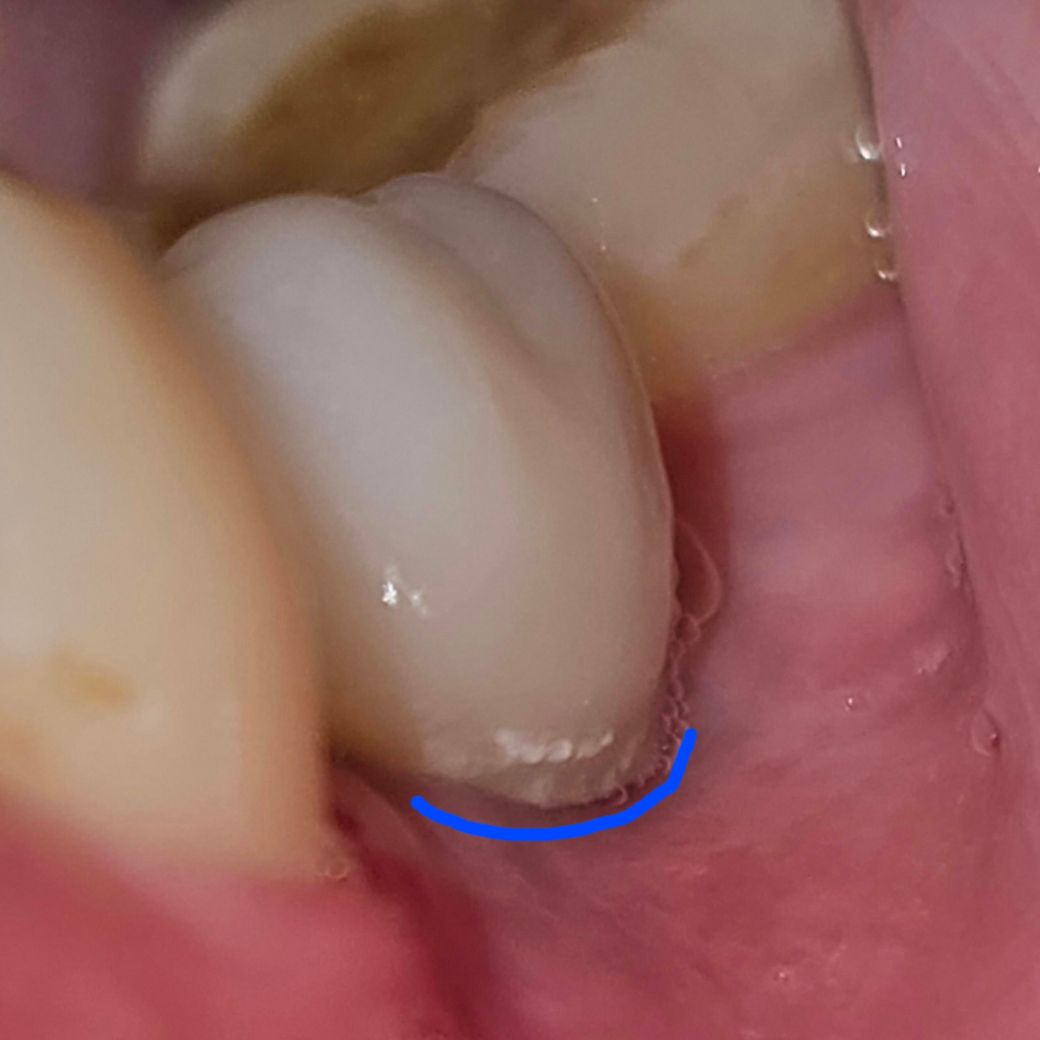

사진에 표시한 것처럼 잇몸 경계면 라인을 따라서 치석이 쌓였길래

플라스틱 이쑤시개로 위아래 양옆으로 마구 긁었는데 괜찮을까요?

안 떨어져서 좀 세게 긁었는데..잇몸 경계면을 따라 긁다보니 잇몸도 좀 같이 긁혔는지 지금 욱신거리네요..

**참고로 긁는 걸로 안 떨어지길래 치약 발라놓고 치간칫솔을 치아 사이에 끼고 잇몸 라인 따라 당기면서 닦았더니 떨어졌습니다..

사진 보면 굳어져 딱딱해 진 것으로 보입니다. 이정도면 본인 스스로 하기 어렵고 치과에 가서 스켈링 하여 제거해야 합니다.